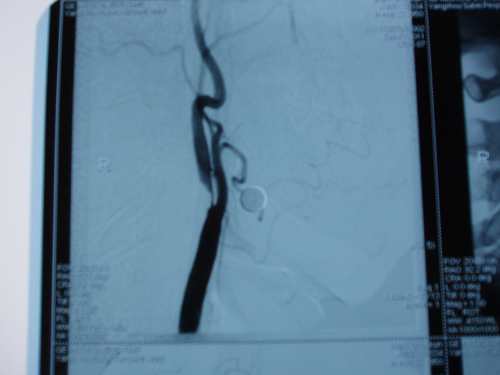

患者一:夏某某,男,62岁,因发现右侧颈内动脉重度狭窄20余天入院。既往糖尿病病史,住院了后行DSA检查示:右侧颈内动脉近段90%狭窄,无明显症状,手术指征明确,故行右侧颈动脉内膜剥脱术。

患者二:徐某某,男,65岁,因发作性头晕一个月入院,既往有晕厥病史,高血压病史20年,糖尿病病史3年,入院后行DSA检查示:左侧颈内动脉重度狭窄,约95%,左锁骨下环状狭窄80%。手术指征明确,于12于17日顺利手术。